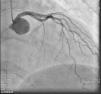

On admission the pain was decreasing; the physical examination was unremarkable, the electrocardiogram showed sinus rhythm, with negative T waves in the inferior leads, and troponin I was positive. The pain eventually disappeared after intravenous nitrates, and she was admitted to the coronary care unit. She underwent coronary angiography (Figure 1, Video 2), which revealed a spontaneous dissection of the posterior descending artery, with TIMI 2 flow, some posterolateral branches visualized from intercoronary collaterals, and severe vasospasm of the proximal right coronary artery (RCA), which reproduced the pain, relieved after intracoronary nitrates. No other unequivocal coronary lesions were noted, although a long dissection of the left anterior descending artery with intact intima cannot be excluded (Online Figure 2). It was decided not to perform percutaneous coronary intervention (PCI), and she was kept in the ward anticoagulated with subcutaneous enoxaparin (1 mg/kg twice daily), with dual antiplatelet therapy and a calcium channel blocker. Screening for autoimmune disease was negative. There were no events during hospitalization and she was scheduled for an angiographic review a week later, which showed progression of the dissection, with a wider false lumen (Figure 2, Video 3). Pain recurred during the procedure and a dissection was noted in a posterolateral branch. It was decided to perform PCI, and two bioabsorbable vascular scaffolds (BVS) were implanted in the PDA, guided by optical coherence tomography (OCT) coregistered with angiography. A third BVS was implanted in the distal RCA due to proximal progression of the dissection. A bare-metal stent was also implanted in the ostial RCA due to a traumatic dissection induced by the guiding catheter. Comparison of the images from angiography and OCT reveals a discrepancy in total (false plus true) diameter in the distal RCA (Figure 3, Video 4). After the procedure the patient was asymptomatic, although with a significant residual dissection in the RCA and posterolateral branch (Video 5). Anticoagulation was suspended and she was discharged five days later, with no further episodes of chest pain. Four months after this episode, she has had no recurrence of pain and is asymptomatic.

Figure 2.

Second angiogram of the right coronary artery, showing a wider false lumen in the posterior descending artery, greater true lumen compromise and worse flow to the posterolateral branches.